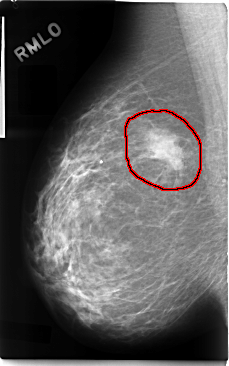

C_0094_1.RIGHT_MLO

FILE: C_0094_1.RIGHT_MLO.OVERLAY

TOTAL_ABNORMALITIES 1

ABNORMALITY 1

LESION_TYPE MASS SHAPE IRREGULAR MARGINS ILL_DEFINED

ASSESSMENT 5

SUBTLETY 5

PATHOLOGY MALIGNANT

TOTAL_OUTLINES 1

BOUNDARY